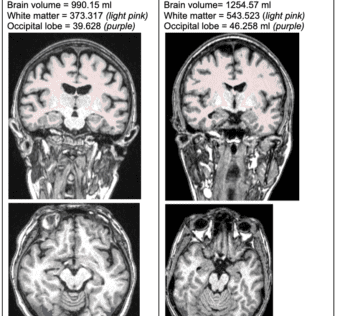

Research Reveals Link Between Type 2 Diabetes and Brain AgingHIT Consultant - (Thursday December 5, 2024) - Frequent Updates/ HIT Consultant | |

![]() | What You Should Know: – Prenuvo, a provider of proactive whole-body MRI scans, has presented groundbreaking research at the Radiological Society of North America (RSNA) 2024 Annual Meeting, revealing a significant link between Type 2... Groundbreaking research presented by Prenuvo at RSNA 2024 reveals a significant link between Type 2 diabetes and brain volume loss. Analyzing over 650 participants, the study highlights that diabetes is associated with reduced white matter in the occipital lobe, raising concerns about cognitive decline. This underscores the need for comprehensive screening beyond traditional tests to enhance early intervention strategies. As we uncover these critical insights, it's vital for healthcare IT professionals to integrate advanced imaging technologies and AI-driven analysis into patient care to improve outcomes.#HealthcareIT #DiabetesResearch #BrainHealth #MRI #ArtificialIntelligence #CognitiveDecline #PatientCare As a healthcare IT expert, write a 100-word extractive summarization based on a blog post from the given text for posting on LinkedIn. The summary should capture key ideas from the entire post and its headings while staying focused, clear, and engaging. Use 5-7 relevant and popular online hashtags that are most likely to drive visibility and engagement. Avoid adding URLs or calls to action, and ensure the language is optimized for LinkedIn engagement style with a variable potential hook or attention-grabbing statement. The target audience is other healthcare IT professionals. Following is the title and text. { "id": "chatcmpl-Ab4pBYobtmzGQhVsQXC8VTDgbPniD", "object": "chat.completion", "created": 1733400045, "model": "gpt-4o-mini-2024-07-18", "choices": [ { "index": 0, "message": { "role": "assistant", "content": "Groundbreaking research presented by Prenuvo at RSNA 2024 reveals a significant link between Type 2 diabetes and brain volume loss. Analyzing over 650 participants, the study highlights that diabetes is associated with reduced white matter in the occipital lobe, raising concerns about cognitive decline. This underscores the need for comprehensive screening beyond traditional tests to enhance early intervention strategies. As we uncover these critical insights, it's vital for healthcare IT professionals to integrate advanced imaging technologies and AI-driven analysis into patient care to improve outcomes. nn#HealthcareIT #DiabetesResearch #BrainHealth #MRI #ArtificialIntelligence #CognitiveDecline #PatientCare", "refusal": null }, "logprobs": null, "finish_reason": "stop" } ], "usage": { "prompt_tokens": 487, "completion_tokens": 130, "total_tokens": 617, "prompt_tokens_details": { "cached_tokens": 0, "audio_tokens": 0 }, "completion_tokens_details": { "reasoning_tokens": 0, "audio_tokens": 0, "accepted_prediction_tokens": 0, "rejected_prediction_tokens": 0 } }, "system_fingerprint": "fp_3de1288069" } Prompt Tokens - 487 |